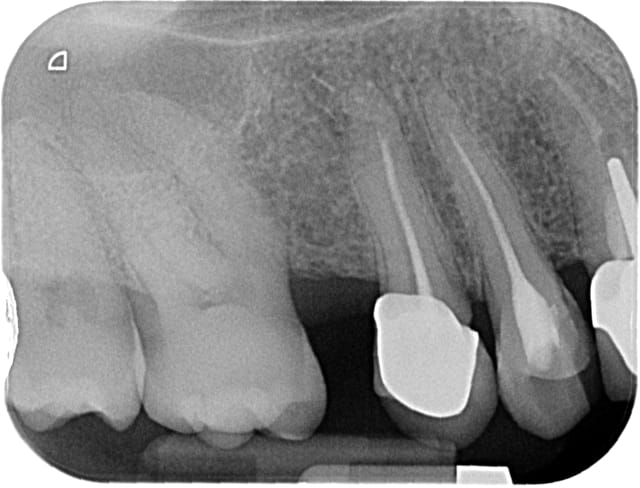

Mais sans radios c'est difficile.

11 et 21 sont vitales.

pour le haut je ne suis pas sur que la forme de la 12 soit très esthétique,

ainsi est-ce que refaire la 12 et cc pour 22 21 11 parait pertinent ?

sauf que si on refait 12 en gardant l'inlay-core ( je suis toujours prudent avec les déposes !!), cela vaut-il le coup de faire des cc ?